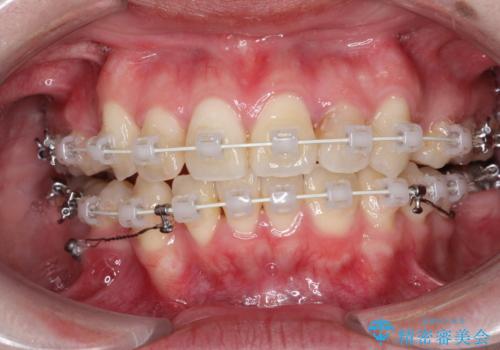

- 矯正装置

- 審美装置

- 治療期間

- 2年

ブリッジを装着している歯は動かすことができないので、矯正前に除去する必要があることがあります。

今回の場合も、ブリッジを除去して矯正後にセラミックブリッジを装着しました。